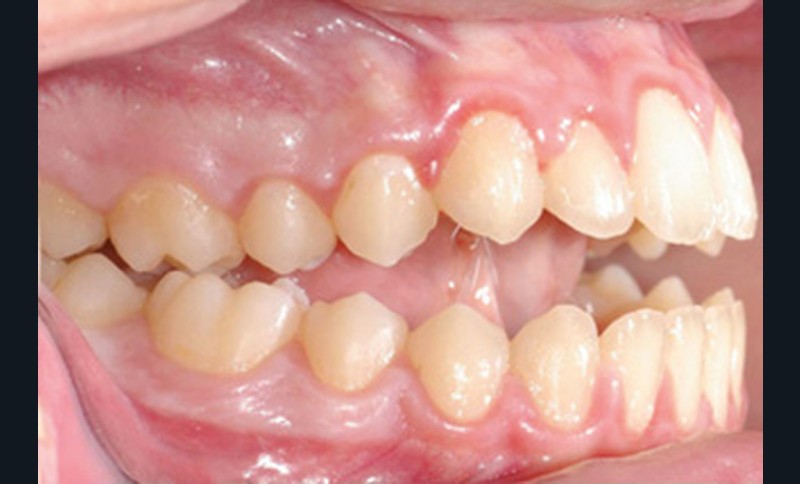

Quelques années plus tard, au moment de démarrer sa prise en charge orthodontique, la patiente présentait à nouveau une béance antérieure, un décalage des milieux incisifs de 2 mm et le problème transversal avait récidivé. Lors de l’examen clinique, elle présentait un inversé d’occlusion bilatéral postérieur et une ventilation buccale exclusive. À la suite du refus de réaliser l’amygdalectomie de façon précoce, elle ronflait toujours et sa déglutition ne s’était pas modifiée malgré des séances d’orthophonie (fig. 7 à 15).